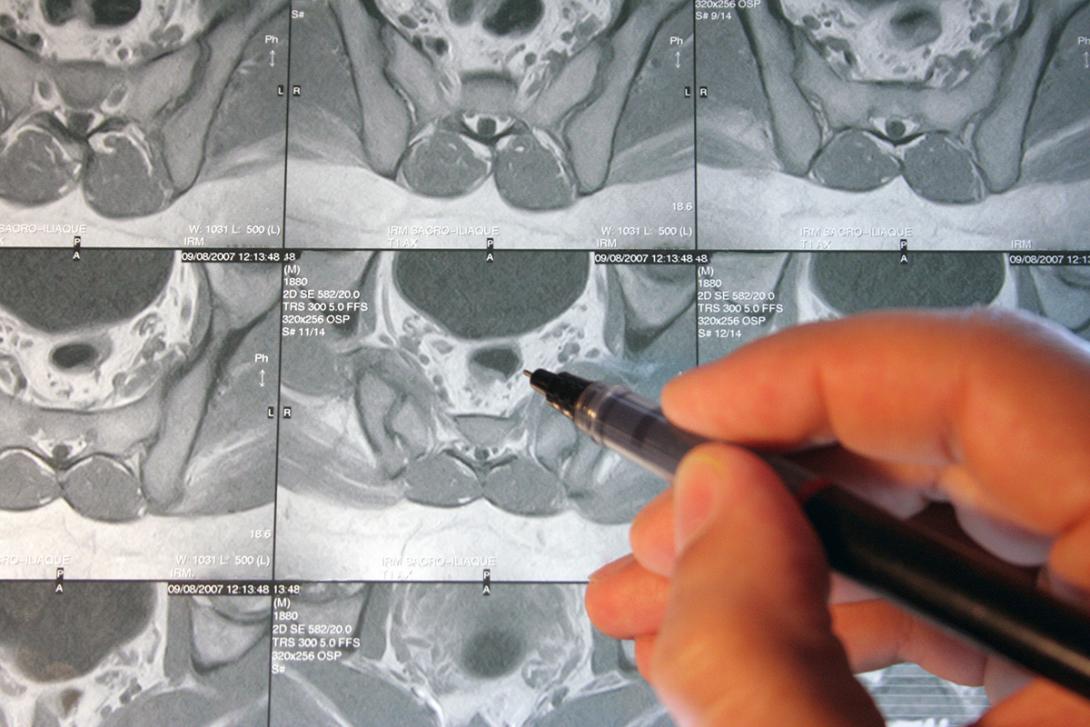

IRM dynamique

L’IRM dynamique est également appelée déféco-IRM. L’IRM est une Imagerie par Résonnance Magnétique : il s’agit d’un examen de radiologie sans irradiation (pas de radiation ionisante), et sans injection de produit intra-veineux.

Objectif : Son but est de bien étudier l’anatomie des organes du pelvis (vessie, utérus, vagin, colon, rectum, sphincter anal), d’abord de manière statique, puis de manière dynamique, c’est-à-dire en mouvement. Cela permet d’identifier et de bien étudier la présence et l’importance des troubles de la statique pelvienne : prolapsus vaginal (cystocèle, hystéroptose, rectocèle) et prolapsus rectal.

C’est un examen primordial pour bien étudier le type de trouble de la statique et guider l’équipe chirurgicale dans le traitement et notamment en cas de chirurgie nécessaire.